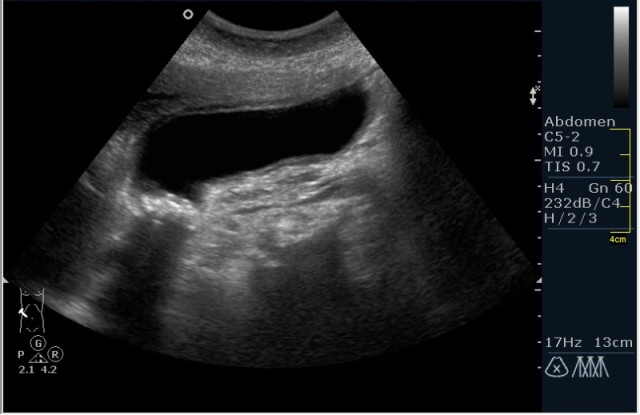

Пациент с болями в эпигастрии

Диагноз не сложен. Как вы думаете, что необходимо рекоммендовать именно при такой картинке?

острый калькулезный холецистит

Без сомнений, вопрос касался рекоммендации. При таких множественных мелких конкрементах, желательно выполнение интра-операционной холангиографии, для исключения наличия конкрементов общего жёлчного протока.